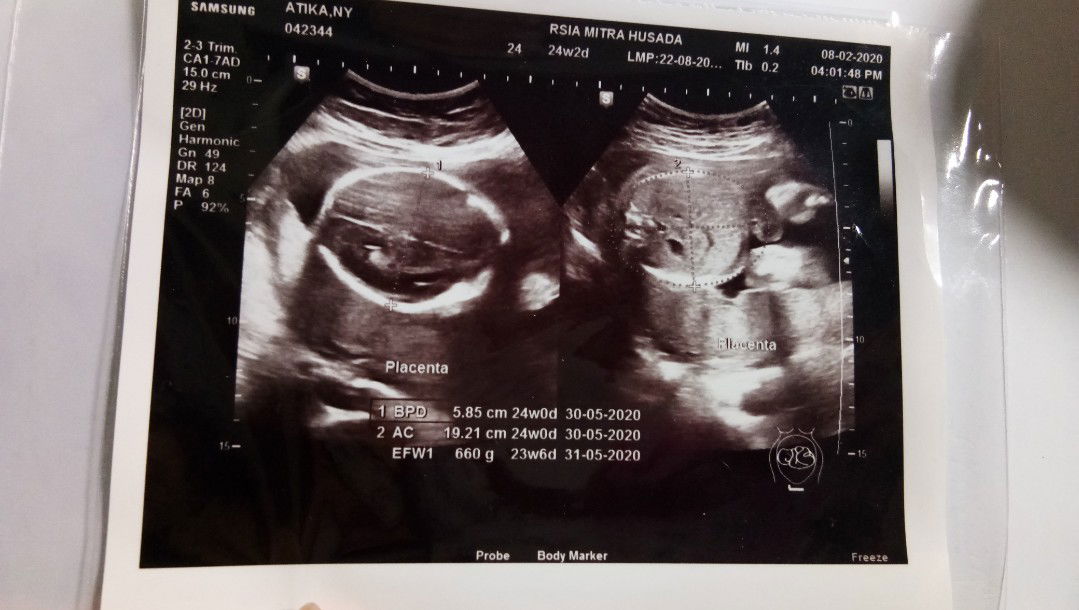

Letak plasenta

Assalamualaikum Bunda2.. Saya hamil 24 w, kemarin pas USG dokter bilang plasentanya tidak menyenangkan karena ada di bawah.. Dokter bilang semoga segera geser ya.. Biar posisi kepalanya dedek bisa di bawah.. Nah, apakah bunda2 ada yg punya pengalaman sama? Apakah plasentanya masih bisa geser bun? Apakah bisa lahiran normal? Tolong tanggapannya ya bunda2.. Terimakasih.. Wassalamualaikum ☺